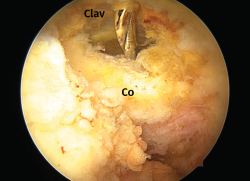

Figura 1. Caso demostrativo de la luxación con la sujeción por parte del paciente de 2 kg de peso.

La exploración clínica se realizó mediante la valoración del denominado signo de la “tecla” (desplazamiento vertical) y del desplazamiento horizontal. Se completó el diagnóstico mediante radiografía simple anteroposterior (AP) comparativa de ambos hombros. En los casos de duda en relación con el grado de la lesión, esta proyección se realizó con la sujeción por parte del paciente de 2 kg de peso (Figura 1). No se creyó necesaria la realización sistemática de tomografía axial computarizada (TAC) ya que la exploración y la exploración bajo anestesia permiten establecer las direcciones y la importancia del desplazamiento. Tampoco se realizó resonancia, dado que la artroscopia permitiría, como así se demostró, diagnosticar posibles lesiones asociadas.